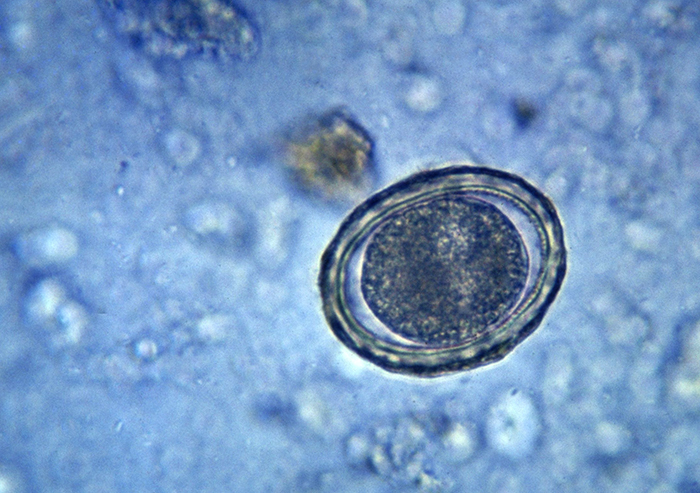

Самым часто используемым способом диагностики является исследование фекалий, которое проводится 2-3 раза с небольшими интервалами. При микроскопическом анализе в кале обнаруживаются зрелые особи, яйца и личинки паразитов.